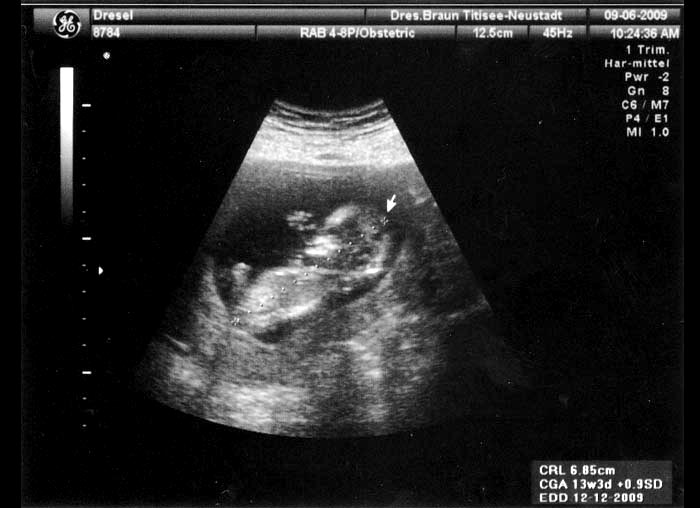

8. Ultraschallaufnahme